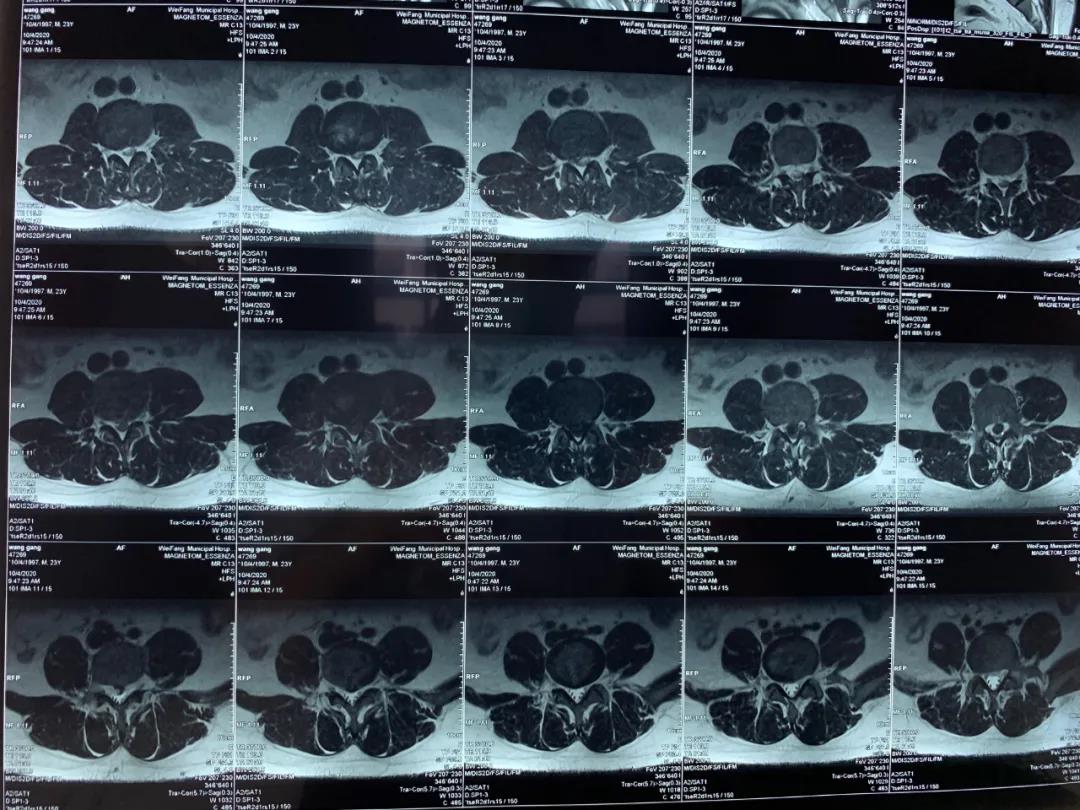

今年23歲的王先生因腰痛伴雙下肢放射痛及麻木不適2年加重5個(gè)月入院,入院后依據(jù)詳細(xì)查體和完善相關(guān)檢查,診斷為:腰椎間盤脫出癥,磁共振提示腰椎間盤巨大脫出。

為緩解王先生的癥狀,許冬雷主任團(tuán)隊(duì)經(jīng)過周密術(shù)前討論,為其制定了UBE(單邊雙通道內(nèi)鏡微創(chuàng)技術(shù))治療方案。10月6日完善各項(xiàng)術(shù)前準(zhǔn)備后,在許冬雷主任和他的手術(shù)團(tuán)隊(duì)共同努力下行經(jīng)后路單邊雙通道(UBE)腰椎脊柱內(nèi)鏡下椎管減壓腰椎間盤脫出髓核摘除及椎間盤射頻消融術(shù),術(shù)后患者痛疼麻木癥狀完全消失,第二天正常適量下床活動(dòng),手術(shù)達(dá)到令人滿意的效果。微創(chuàng)、安全、高效的手術(shù)效果獲得了患者及家屬的一致稱贊。